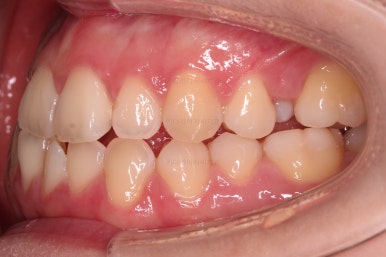

초진 시, 입안의 모습입니다.

아래 중앙선이 윗니의 정중선에 비해 우측으로 많이 쏠려있고요.

전반적으로 아래 치열이 우측으로 가 있어서 특히 송곳니 부분에서의 반대교합이 두드러졌어요.

(아래 송곳니가 위 송곳니보다 밖에 나와있는 상태)

폭이 맞아지고 치아 배열을 조금 시행하니 송곳니 부분에서의 반대교합이 금새 개선된 것을 알 수 있으실거에요.

가지런한 느낌, 교합, 중앙선, 반대교합 등 모든 면에서 개선이 되었고요.